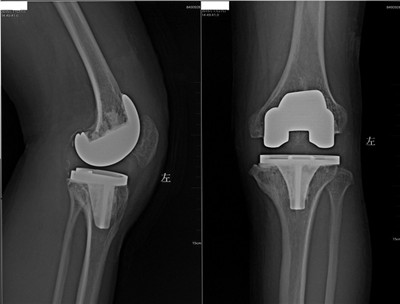

近日在骨二科徐思越副主任医师治疗组收治的一例血友病性关节炎患者的膝关节置换术中,一如既往地贯彻了个性化治疗、术前周密准备的传统。这位青年男性患者数年前因为血友病性巨大假瘤侵蚀膝关节骨质,不得不行右下肢膝上截肢,现在又由于严重的左膝血友病性关节炎承受着严重的膝关节疼痛。这位患者的膝关节骨质发育不良,且胫骨侧骨质严重缺损,并伴有屈曲挛缩畸形。对这样特殊的血友病性关节炎病例,是行技术要求高、围手术风险大的膝关节置换术;还是做风险较小,比较“稳妥”的膝关节融合术?

术前李浩鹏主任医师与主管医师徐思越副主任医师、张廷主治医师反复讨论、推敲,从麻醉方式、假体选择、围手术期凝血因子补充、手术备选预案、术后引流方式、术后康复计划一一落实。值得一提的是,术前应用先进的3D打印技术原大重建了患膝关节模型,对我们推演手术步骤、充分预计手术中可能出现的状况,起到很好的辅助作用。

正是术前付出的辛勤准备,让手术过程流畅平稳。在李浩鹏主任医师、徐思越副主任医师主刀,张廷主治医师协助下,手术已顺利完成,术后患者恢复平稳,患者正按原计划积极康复中。